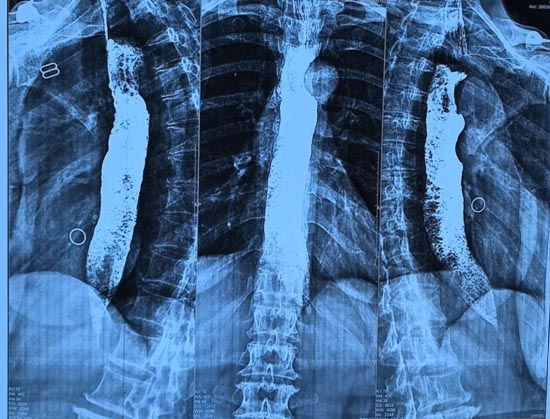

几经周折,蔡阿姨来到靖江市人民医院消化内科门诊就诊。消化内科主任沙杰接诊后,第一时间为她安排了胃镜检查。镜下发现,蔡阿姨的食管已明显扩张,管腔内堆满了长期滞留的食物残渣。内镜团队耐心细致操作,耗时近一小时,才将食管彻底清理干净。为了精准找到病因,医院进一步为蔡阿姨完善了高分辨率食管测压和上消化道造影检查。造影图像上出现了典型的“鸟嘴征”,结合测压结果提示食管下括约肌松弛障碍,最终明确诊断:贲门失弛缓症。

上消化道造影检查

•上消化道造影:可见特征性“鸟嘴征”,贲门通过受阻、食管上段扩张。